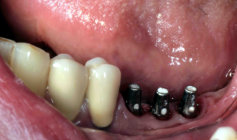

Implantate mit Aufbau für Kronen

mit Kronen versorgte Implantate